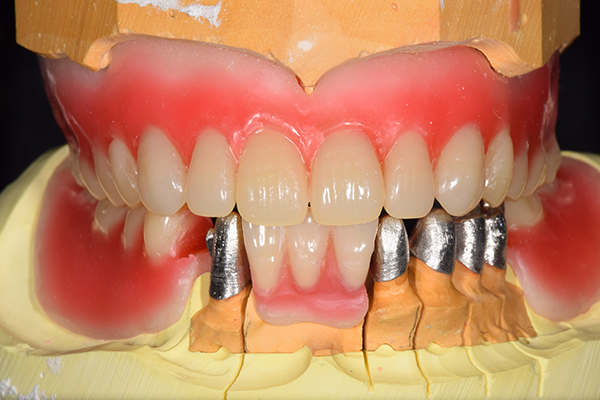

8.患者様のお口に入れて修正

この写真は、実際にお口の中にいれてみて、噛み合わせのチェックを行い、調整したものになります。 上下の入れ歯で青い点、赤い点がはっきりあり、これはしっかり奥歯で噛めるというサインになります。 また、入れ歯自体の大きさや、違和感が強くないか、お顔と調和しているか、唇との関係などをみていきます。もし、ここで大きな修正が発生する場合はもう一度お時間をもらって次回再度確認させて頂きます。 これで修正が終わったら、その模型を技工所に送り、入れ歯を完成させてもらいます。

噛み合わせチェックでしっかり奥歯で噛めるようにし、 歯を並べます。 その後、それに合わせて前歯を作っていきます。